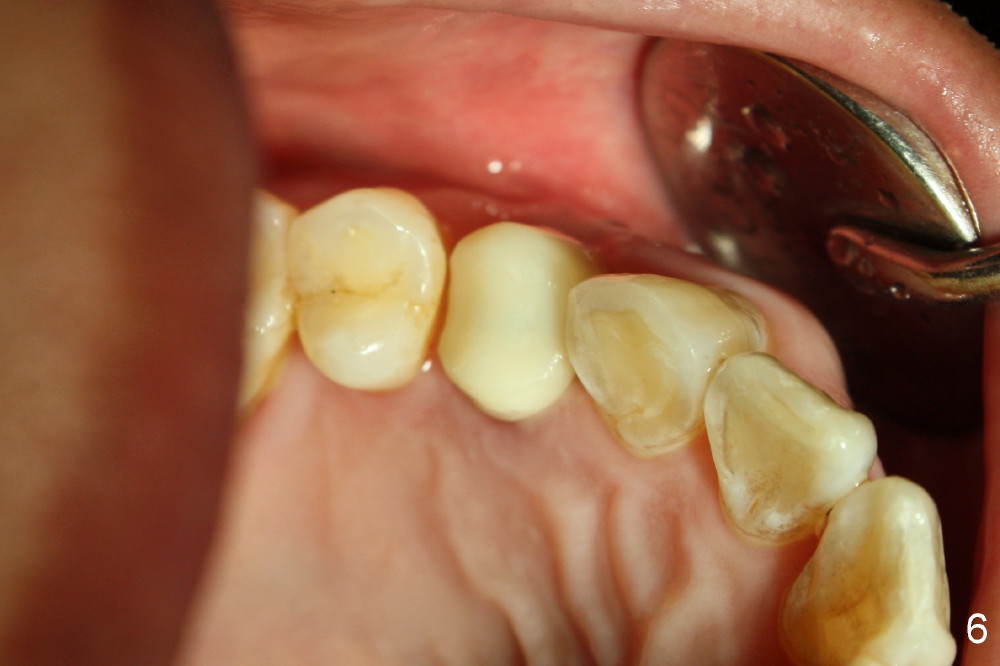

A 56-year-old man fractures the lingual cusp of the upper right 1st premolar (Fig.1,2).

Five days later, the gingiva around the provisional returns to normal color (Fig.5,6, as compared to Fig.3,4). There is minimal postop pain in spite of difficult exodontia.

The patient returns 6 months postop for impression of a permanent restoration. The gingiva with knife-edged papillae adapts to the provisional (Fig.7). The gingiva looks healthy when the provisional is removed (Fig.8). The buccal bone resorption seems to be minimal, as compared to Fig.1,2. There is no bone loss between immediately postop (Fig.9 I; implant), 4.5 months postop (Fig.10 A: abutment), 4 and 7 months post cementation (Fig.11,12 C: crown). Soft and hard tissue morphology remains normal 7 months post cementation (Fig.13). No bone loss is observed 15 months post cementation (Fig.14). The papillae (Fig.15) and bone (Fig.16,17) remain stable 29 months post cementation.